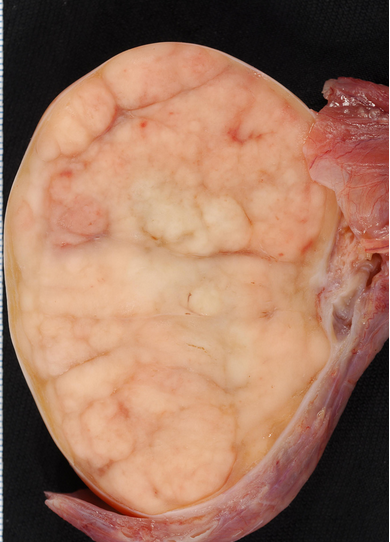

• Teratomalar həm qadınlarda, həm də kişilərdə eyni tezlikdə rast gəlinir, əksəriyyəti ön divarararlığında yerləşir və tərkibində ektodermal mənşəli toxumalar (diş, saç və sümük) rastlanır. Xoşxassəli gedişə malikdirlər, adətən AFP və betta-HCG artmır. Diaqnozunu KT ilə dəqiqləşdirmək mümkün olur (diş, kalsifikasiya). Malign potensialını nəzərə alaraq total cərrahi çıxarma tövsiyə edilir (Şəkil 24a,b,c).

Şəkil 24. Teratoma. A - KT görüntüsü

B - makropreparat

C - tərkibində ektodermal  toxumalar